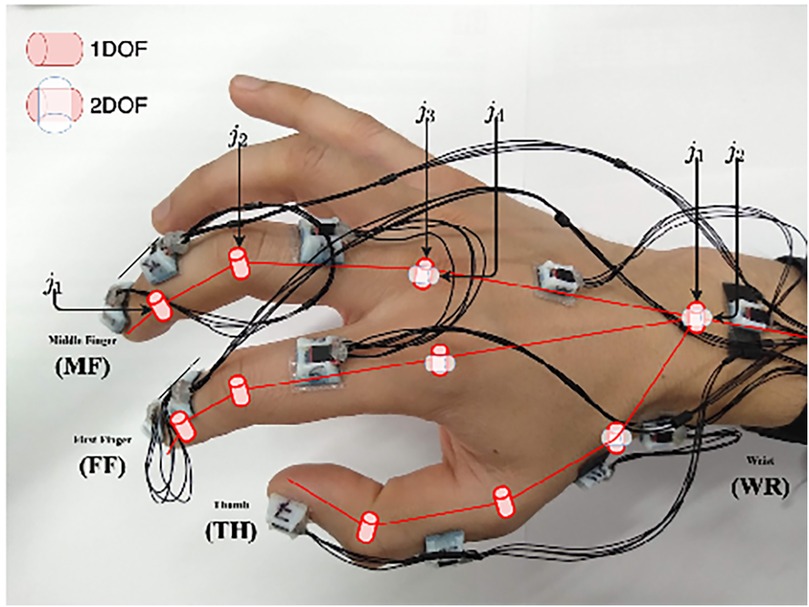

Inertial sensors track motion based on the principle of inertia, which states that an object continues to move unless acted upon by an external force. These wearable sensors include accelerometers (tracking linear acceleration), gyroscopes (measuring angular velocity), and magnetometers (detecting magnetic field changes) (102). These different components are typically integrated into an inertial measurement unit (IMU) when used to detect human motion and posture to increase the accuracy of their measurements (102). The application of inertial sensors has been shown to be successful, with Sani et al. using a chain of 12 IMUs for surgical hand tracking (Figure 9) (5). These wearable IMUs focus on accurately tracking 4 main motions: joint angles of the digits and wrist, global hand position and orientation, global instrument position and orientation, and jaw angle of surgical instruments. The goal was to increase the degree of freedom to allow for smoother and more natural movements by the surgeon (5). Given that the index, middle finger, and thumb are the significant contributors to fine grasping and the use of the surgical instruments (in this case, Castroviejo needle-holder and forceps), each finger was tracked by 3 separate IMUs. The wrist joint was tracked via 2 IMUs, a reference point IMU on the forearm and one on the palm, with the rest of the IMUs being placed strategically to capture the best movements of the remaining joints of the hand.

Figure 9. Inertial sensors. Sani et al. (5) have used inertial sensors for recording and mapping a surgeon's hand's gross and fine motions during cardiac microsurgery. This figure is a pictographic representation of the 12-unit-IMU sensor device used in this study. Each sensor is attached to a specific joint to allow precise measurement of position change. The DIP and PIP joints are represented by j1 and j2, respectively. The axes of the MCP joint are represented by j3 and j4. DIP, distal interphalangeal joint; IMU, inertial measurement unit; MCP, metacarpophalangeal joint; PIP, proximal interphalangeal joint. Used with permission from Sani MF, Ascione R, Dogramadzi S. Mapping Surgeon's Hand/Finger Motion During Conventional Microsurgery to Enhance Intuitive Surgical Robot Teleoperation. ArXiv. 2021;abs/2102.10585.

The Polaris Spectra (Northern Digital Inc.) optical sensors were used to precisely track global hand position and orientation, with infrared markers attached directly to the Castroviejo surgical instruments and the surgeon's wrist (5). A significant disadvantage of the IMU system, however, is the accumulation of small errors in position estimation over time, leading to a reduced accuracy of tracking. These sensors typically drift over time and are sensitive to surrounding magnetic interference. To mitigate this issue, this study attempted to decrease drift by measuring relative angles between IMUs; in addition, they recalibrated the recordings every 5 min (5). IMU sensors have also been combined with optical tracking methods to overcome the line-of-site barrier associated with optical tracking methods (103).